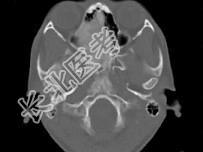

- 单项选择题女,17岁, 鼻阻塞、头痛两年.如图所示符合筛骨病变最可能的诊断是 ( )

B、纤维异常增殖症

E、骨化性纤维瘤